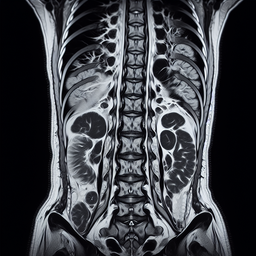

МРТ здухвинно-крижових сполучень

Магнітно-резонансна томографія (МРТ) здухвинно-крижових сполучень – це неінвазивний метод діагностики, що дозволяє отримати детальні зображення цих суглобів і прилеглих структур за допомогою магнітного поля і радіохвиль.